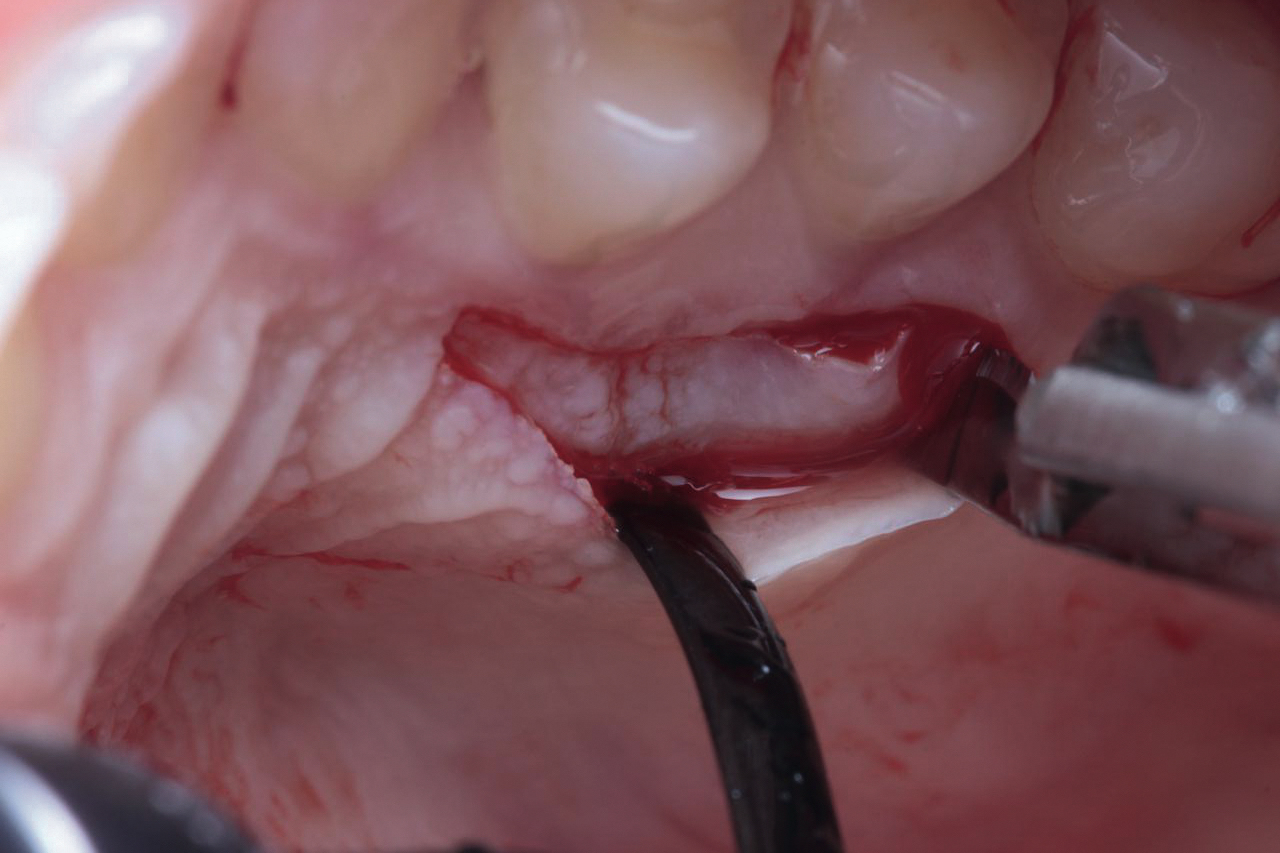

• Соединительнотканный трансплантат (СТТ)

• Получение СТТ

• Твердое небо и бугор верхней челюсти

• Защита донорской области